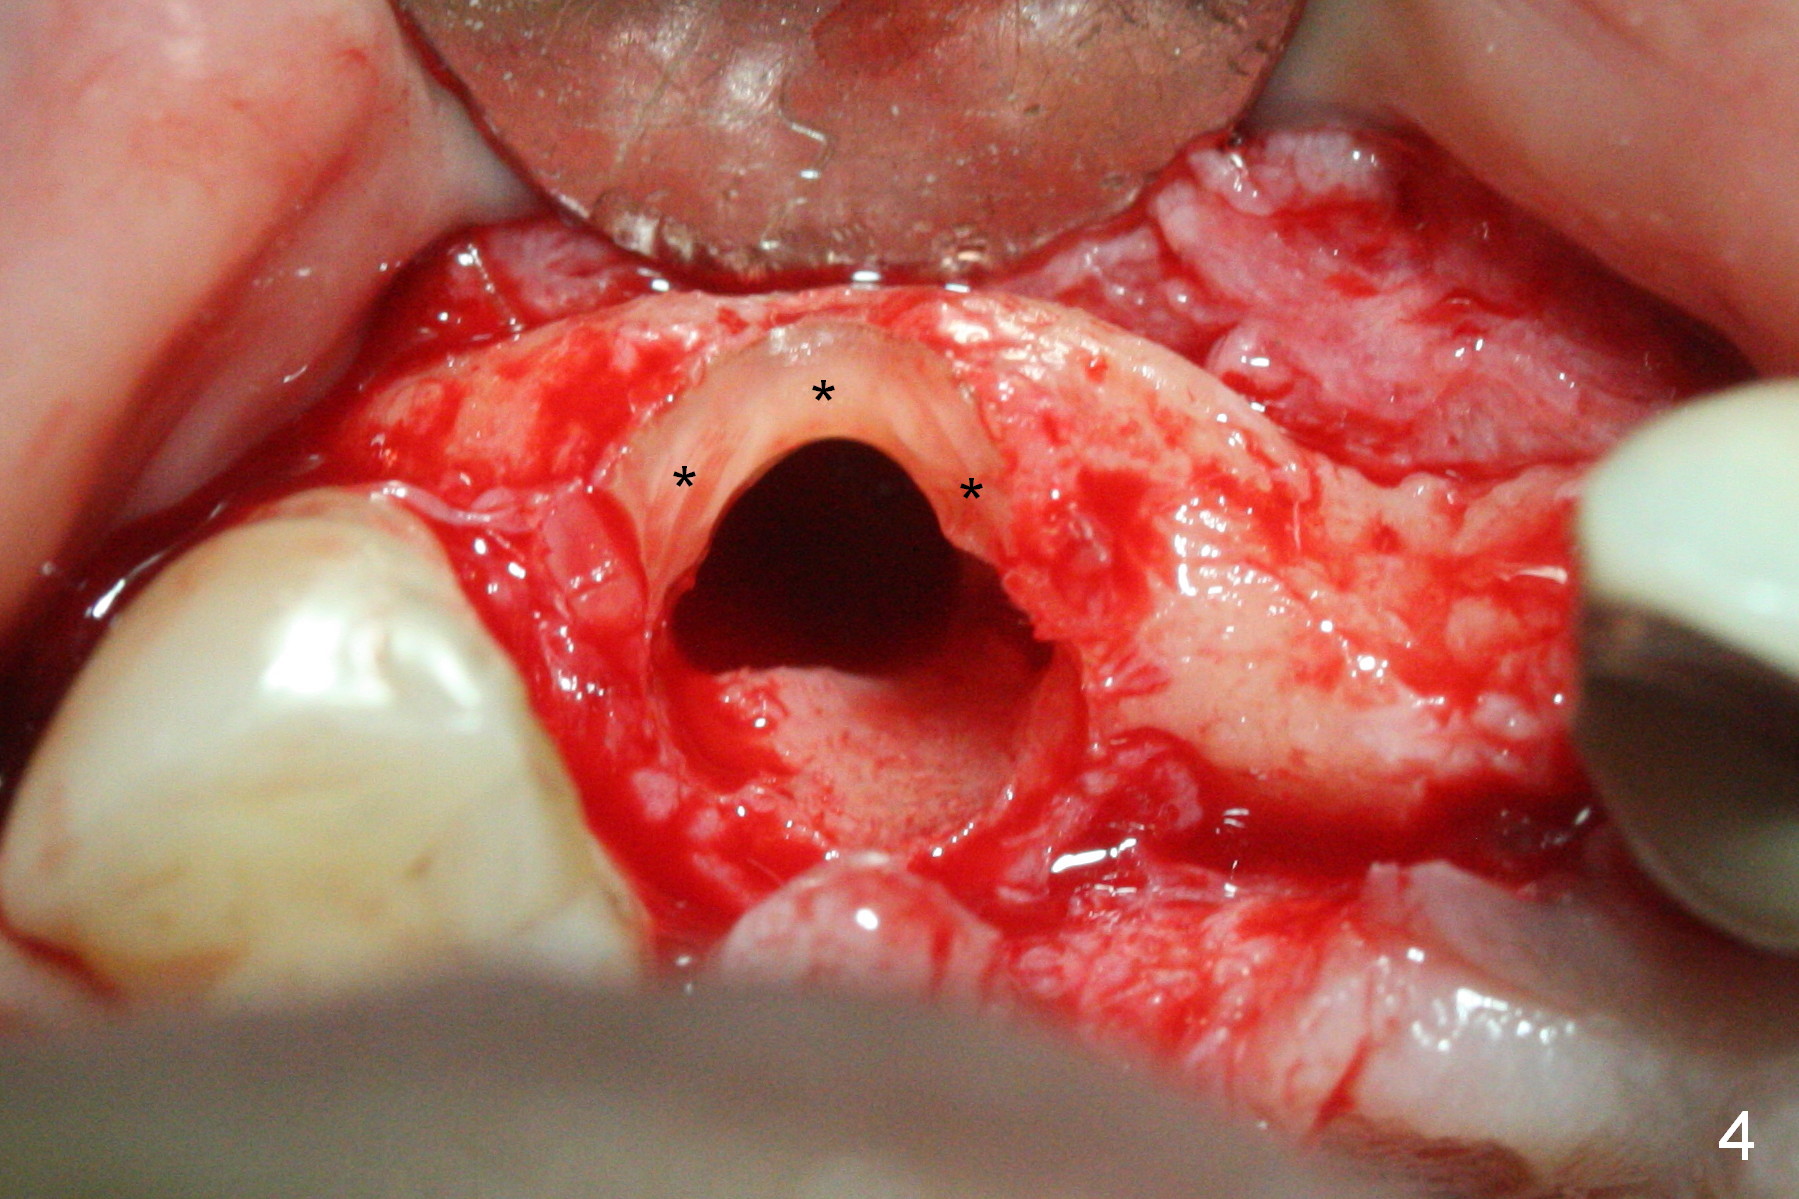

When the bridge is sectioned between #7 and 8, the tooth #6 is found non-salvageable (Fig.1). Incision shows the atrophic buccal plate at #7 (Fig.2 arrowheads); to prevent the same feature from happening at #6 with thin buccal plate, the most buccal portion of the root is preserved (socket shield (Fig.2-4: *)). The initial osteotomy is established in the palatal slope at #6 (Fig.5 circle) with 1.5 mm drill (Fig.6,7). A portion of the root is visible in Fig.6 (arrowheads). After sequential osteotomy with 2 mm, 3 mm (Fig.8) and 3.2 mm drills, a 4x15 mm implant is placed (Fig.10). To accommodate the cross bite, the coronal portion of the implant (Fig.9 white circle) is positioned close to the socket shield. It appears that the shield prevents the implant from encroaching the buccal plate.